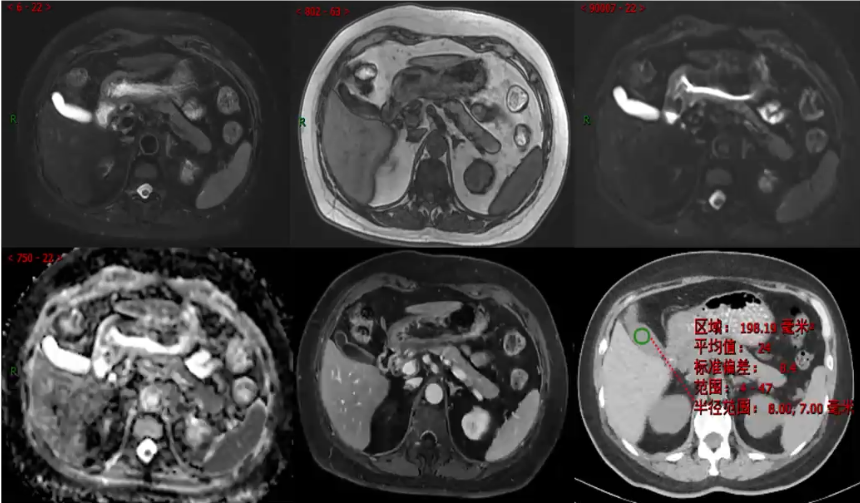

男,58岁,乙状结肠肿瘤支架植入术后复查

来源:《肝脏囊性病变的影像诊断》